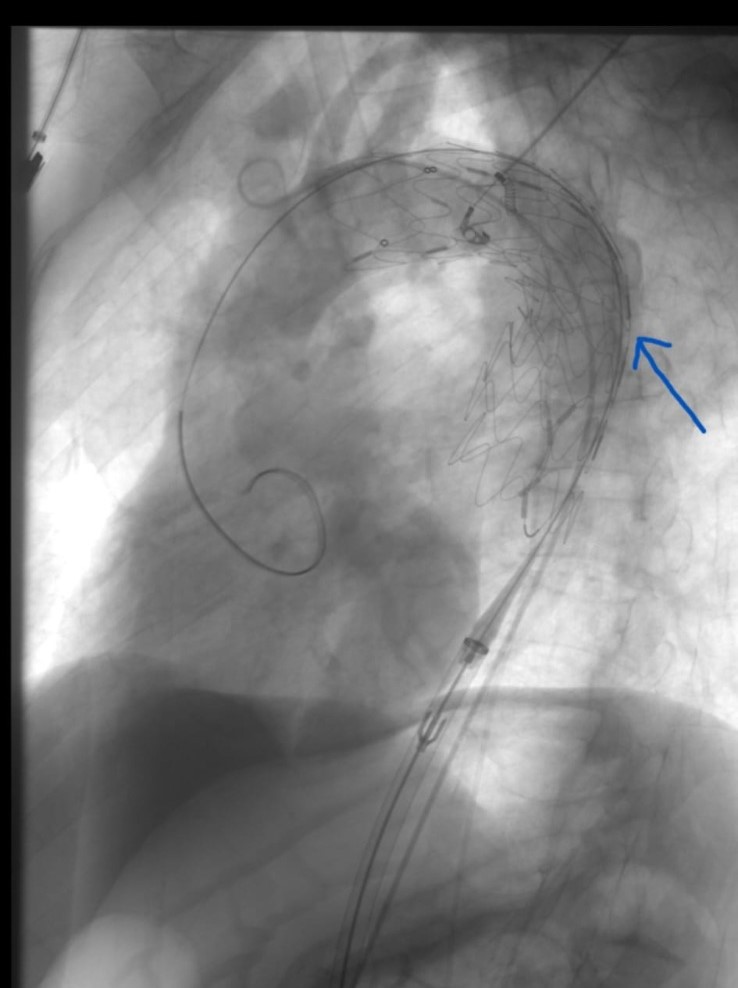

“Aort denilen vücudumuzun en büyük atar damarın karın bölgesindeki balonlaşması genellikle herhangi bir yakınmaya neden olmadan sessizce genişler ve patlamaya yol açar. Bu durumdan muzdarip hastanın %80 i kaybedilir. Ameliyata ulaşmış hastalarında riski yüksektir. Kanamaya yol açmış tüm hastaların en çok %10 ile 20 si taburcu olmaktadır. Risk altındaki kişilerin anevrizma olup olmadığı önceden saptanabilirse cerrahi ya da endovasküler (TEVAR /EVAR) girişim ile yaşam tehlikesi ortadan kalkar. Sigara ve genetik faktörler balonlaşmada rol oynar.65 yaş ve üzeri grupta her 65 erkekten birinde bu hastalık görülür. Erkeklerde bayanlardan 5 kat daha sık görülmektedir. Ülkemizde her yıl 3500 ile 4000 arası kişide tehlikeli balonlaşma olduğu tahmin edilmektedir. 65 yaş ve üzeri erkekler kalp ve damar cerrahisi uzmanına başvurması gerekir. Sigara içiliyorsa veya ömür boyunca 5 paketten fazla içildi ise ailede bu hastalığa sahip olanlar varsa risk daha yüksektir. Basit görüntüleme yöntemleri ile ana damarlarda balonlaşma olup olmadığı saptanabilir. Her balonlaşma girişim gerektirmeyebilir. Damar çapına göre takip edilebilir veya girişim yapılabilir. Çok geniş balonlar açık ya da kapalı yöntemlerle tedavi edilebilir. Hangi yöntemin seçileceğine; kişinin yaşına önemli sağlık sorunların olup olmamasına balonlaşma yerine göre karar verilir.5 yıl önce Türk Kalp ve Damar Cerrahisi Derneği “İçimizdeki Balon” başlıklı halkı bilinçlendirme kampanyası başlatmıştı Karaman’da da son 5 yıldır bu tür balonlaşmalara başarılı şekilde hem açık hem kapalı müdahale edilmektedir. En son 1 hafta önce hem karnında hem de göğsünde tehlikeli balonlaşma görülen A.B.Ç isimli, 65 yaşındaki hastamıza eş zamanlı hem göğüs hem de karın bölgesindeki balona açık cerrahi uygulamadan kapalı olarak başarılı şekilde müdahale edildi. Bu gün ise hastanın taburcu edilmesi planlanmaktadır. Ülkemizde sayılı kliniklerde Kalp Damar Cerrahisi, Girişimsel Radyoloji ve kimi zaman Kardiyoloji tarafından bu tür işlemler yapılmaktadır. Anestezi ve Reanimasyon Uzmanlarından Dr. Öğr. Üyesi Tayfun ET, Uzm. Dr. Mehmet Serdar Şencan ve Beyin Cerrahisi uzmanlarından Op. Dr. Gökhan Reşitoğlu’nun desteği ile anjio odasında kısa sürede gerçekleştirilen hem TEVAR hem de EVAR yöntemi ile eş zamanlı uygulanan endovasküler işleminin Kalp Damar Cerrahları tarafından Karaman’da uygulanabiliyor olması hastamız için büyük şanstır. Geç kalmış olsa da yıllardır kullandığı sigarayı bırakmış olan hastamıza uzun ömürler diliyoruz.”